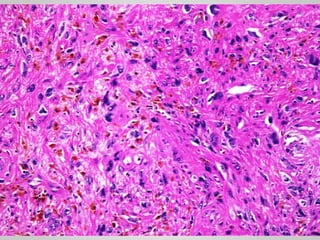

NODULAR FASCIITIS • Self-limited •Fibroblastic and myofibroblastic proliferation • Young adults • Upper extremity • History of trauma • Rapid growth over a period of several weeks or months • Typically no larger than 5 cm • Spontaneously regresses and if excised, it rarely recurs.

• 22.

• Circumscribed, orslightly infiltrative • Arranged randomly or in short fascicles reminiscent of tissue culture fibroblasts • The cells vary in size and shape (spindle to stellate) and have conspicuous nucleoli; mitotic figures are abundant. • Lymphocytes and extravasated red blood cells are common.